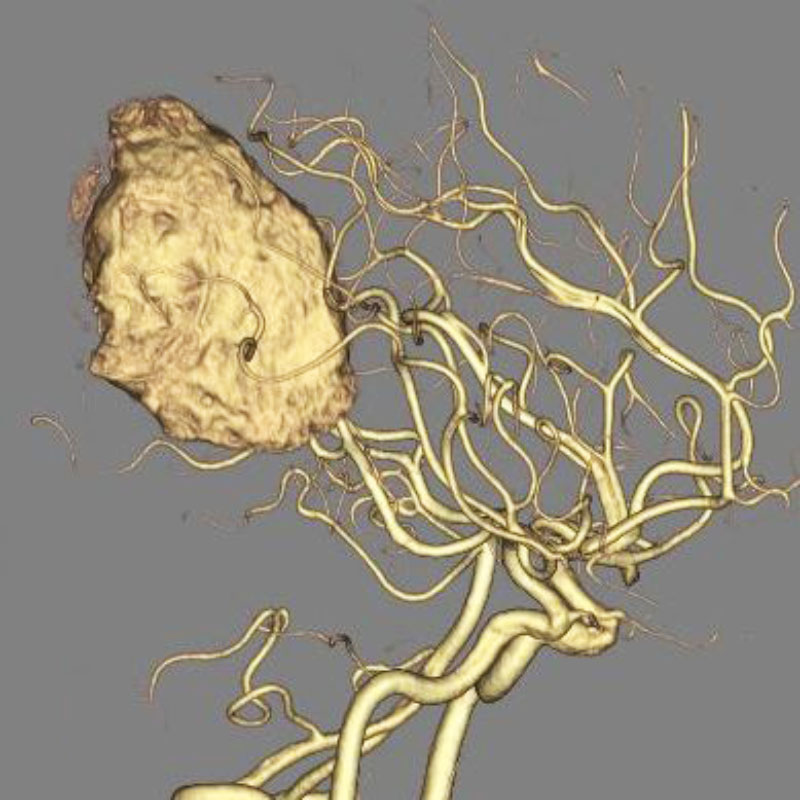

脳動静脈奇形

血管塞栓術

芝野/古谷